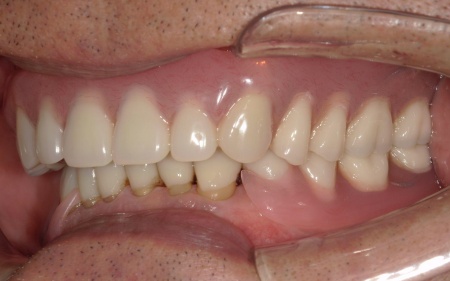

次に上下顎に装着するため、チタン床を使用した金属床義歯を作製しました。

チタンは軽量でありながら強度が高く、体になじみやすい特徴をもつ素材です。また、金属床にすることで従来の樹脂製義歯と比べて薄く作ることが可能になり、装着による違和感の軽減も見込めます。

また、上顎は残存歯が少ないためすべてを覆う総入れ歯で、下顎は前歯がしっかり残っているため部分入れ歯の形で作製しました。

完成した入れ歯を装着していただき、噛み合わせや義歯の安定性、見た目の仕上がりに問題がないことを確認して、治療を終了しています。